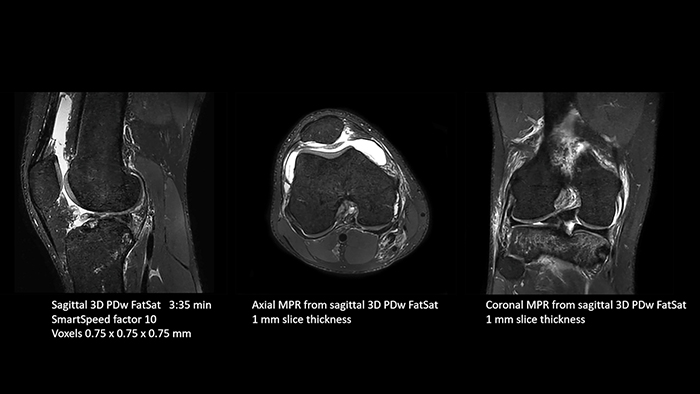

A leap in MSK imaging thanks to SmartSpeed

Previously, the practice wasn’t able to use 3D imaging on all joints, because the time required was too long, and on some joints it was simply not possible to achieve a good quality image, Dr. Schröter says. “Now, with SmartSpeed we consistently use 3D imaging for all joints and can thus discover the smallest changes, for example in the cartilage. And that, of course, helps us in making a detailed diagnosis.” Dr. Schröter says their MSK images show high contrast and extremely high quality. He mentions the menisci as an example. “We use a 3D proton density weighted fatsat sequence, thickness is 0.3 mm and scan time 3 minutes. The MPRs show an unbelievable resolution. Very small tears and even fraying of the tip of the meniscus become visible, which is normally only possible in arthroscopic surgery. When imaging the small joints of the fingers and the thumb we achieve extraordinary quality. Using SmartSpeed we succeed in displaying even very small structures anatomically correct, enabling us to see the extent of possible injuries. Tendons and ligaments appear with higher resolution so we can better see the injury pattern and describe and delimit it. Our referring physicians are fascinated by the extraordinary quality and high level of detail of the images. Patients are happy that the examination does not take too long. We hear from patients that it took a lot less time than they expected. This is especially important when scanning patients who are very uncomfortable in the MRI environment.”

- Traumatic knee injury

SmartSpeed is used to reduce scan times. All three PDw orientations were obtained with only one 3D sequence using SmartSpeed. Performed with 1.5T Ambition X, 16ch dS Knee coil.

- Traumatic knee injury

SmartSpeed is used to reduce scan times. All three PDw orientations were obtained with only one 3D sequence using SmartSpeed. Performed with 1.5T Ambition X, 16ch dS Knee coil.

With these 3D scans we can create freely selectable MPRs that are pin-sharp, allowing us to easily see pathological changes.”